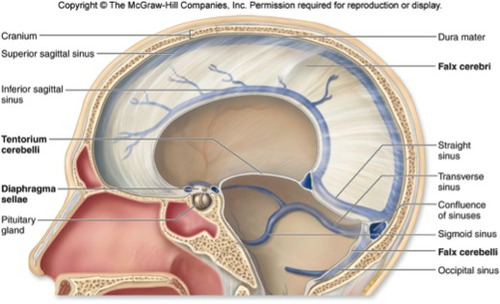

Falx cerebri

Falx cerebelli

Tentorium cerebelli

Diaphragm sellae (near pituitary gland)